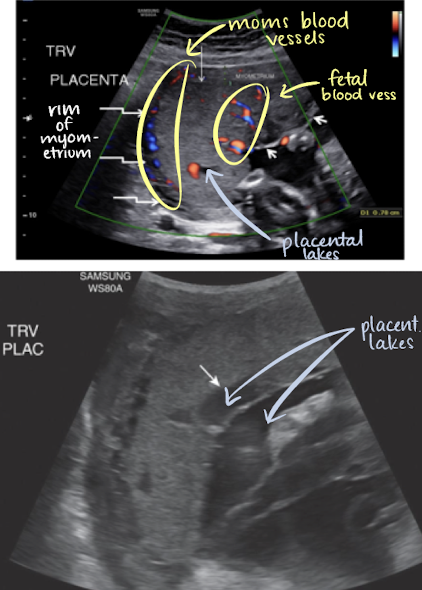

SONO: placenta

homogeneous

pebble-gray—mildly more echogenic compared to uterine wall

may be more echogenic in 1st trimester

smooth borders

highly vascular structure

rim of myometrium outside placenta should be noted

prominent maternal vessels may be seen posterior to placenta (anechoic tubes)

placental lakes may also be seen in placenta